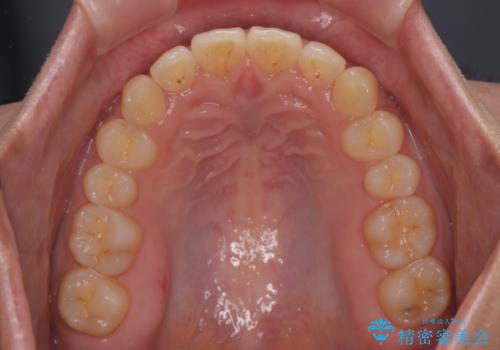

- 下顎前歯が完全に隠れてしまっていることを気にして来院された患者様です。

下顎の臼歯が手前に傾斜していることで咬み合わせが深くなってしまい、下顎前歯が見えないほどに上顎前歯が覆い被さっている状態でした。

下顎臼歯を起き上がらせるためにユーティリティーアーチを使用し、一気に深い咬み合わせを改善することができました。